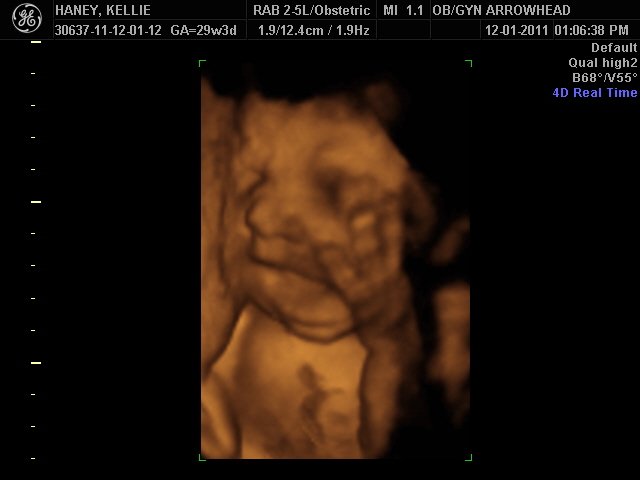

We offer complimentary 3D/4D Ultrasounds to all our OB patients around 30 weeks! The following photos are some examples of our work, shown with permission from our patients.